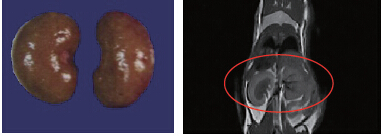

44.8g小鼠,腎臟體積:0.315cm3,解剖體積(水溢法):0.293cm3,成像時間:10min